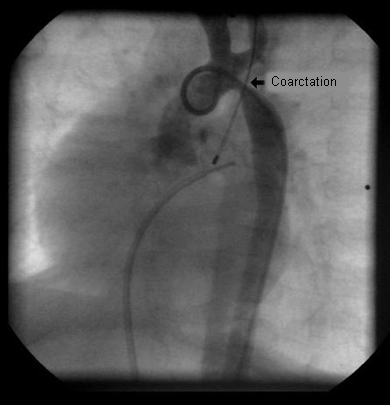

Aortic angiography in an infant after surgical reconstruction of the aortic arch shows marked narrowing at the distal aspect of the surgical repair

From the personal collection of Jeffrey Gossett, MD, Children's Memorial Hospital, Northwestern University, Chicago; used with permission